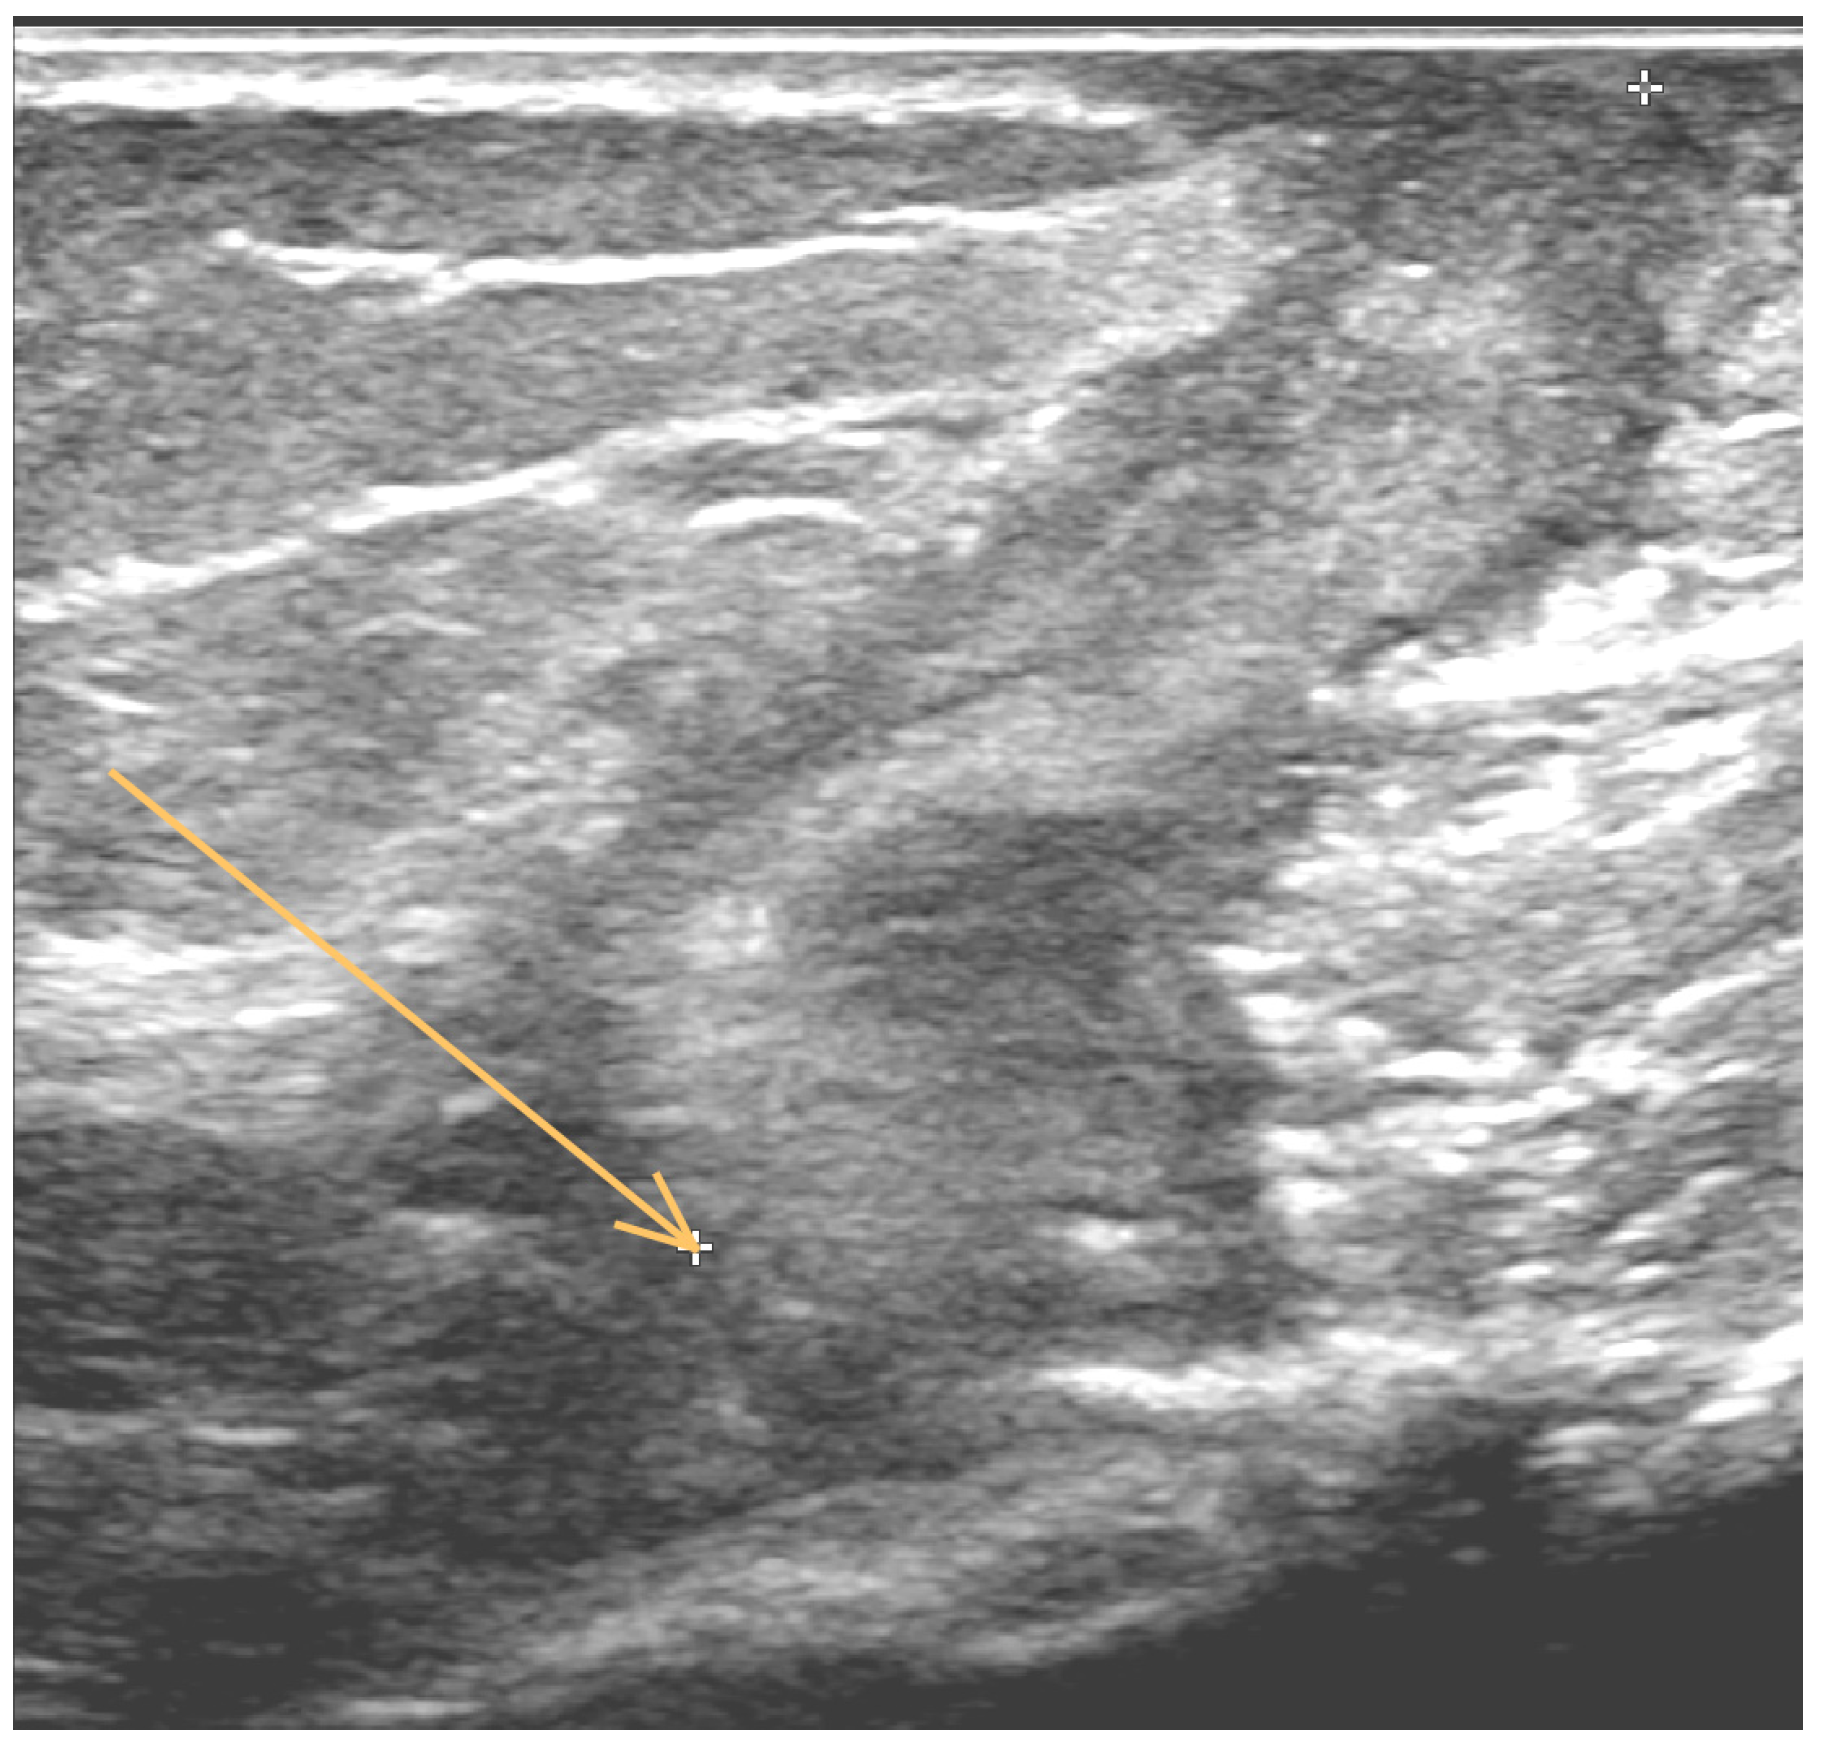

1. Case Report